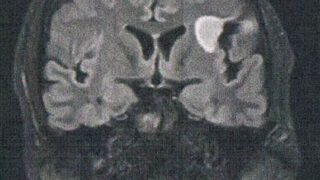

GLIOMA:手術後126ヶ月目の検査

手術から10.5年が経過した。半年ごとの定期検査です。検査概要びまん性星細胞腫グレード2(悪性転化しやすい腫瘍)MRI検査: 造影剤なし / 造影剤あり造影剤ありの場合:4時間前から絶食し、MRIの1時間前に血液検査を済ませる。診断結果MR...